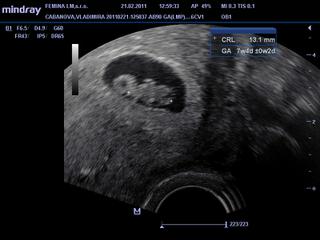

ahojte, uz som tu dlhsie nebola, lebo v skole som od rana do vecera a vybavovacky okolo svadby, vcera som bola na sone a uz miminku bilo srdiecku, vsetko v poriadku, velkost akurat, takze uplne stastna, gynekolog ma konecne nove sono, takze mi dal fotky aj videa na usb kluc 🙂 ...kontrola zase 7.3....priznaky raz za cas ma boli podbrusie, niektore jedla ani vidiet, najma sladke, nepribrala som a ani brusko ziadne....

pripajam vcerajsie sono